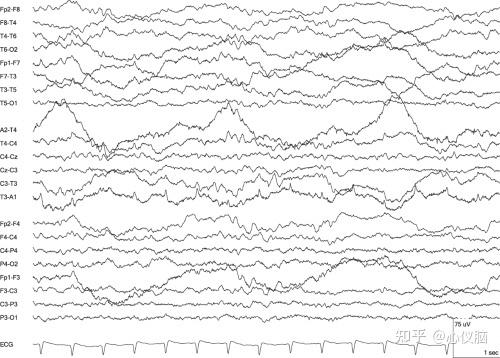

3.心电伪迹

心脏收缩伴随心电图扩展到头部,呈现出的一种有规律且与心跳一致的棘波,常见于颞部导联和耳垂无关电极,主要是由于耳垂参考电极接触不良或参考电极靠近心脏导致。